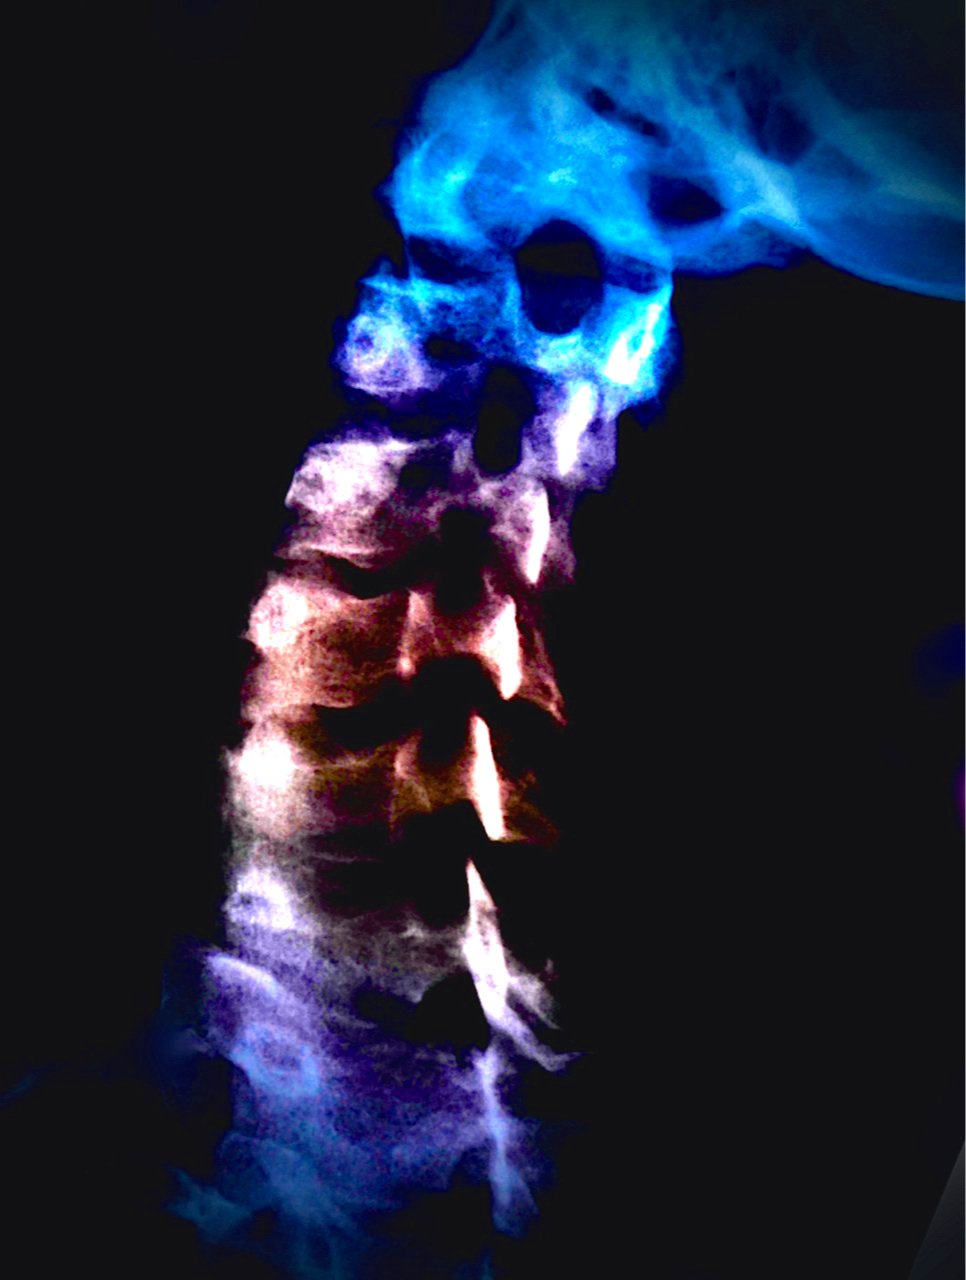

saturday night fever (girl meets boy diptych)

Selected for July/Aug 2022 exhibition in Art No.23’s Barcelona gallery.